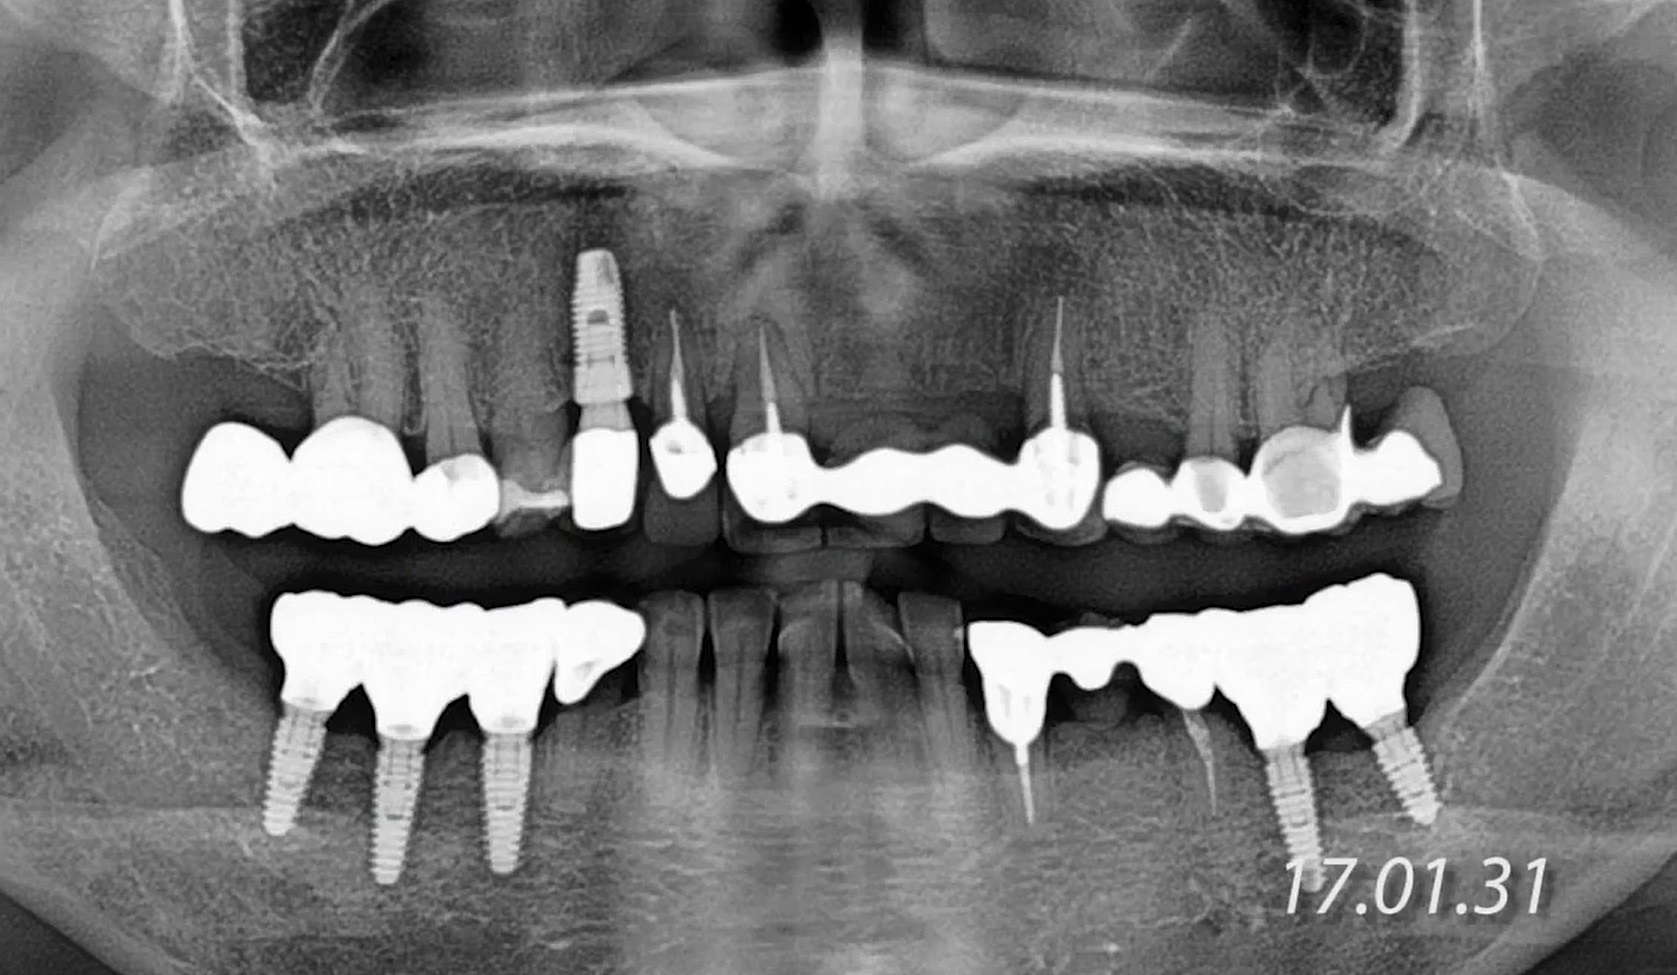

#11,#12,#23,#24 Root Membrane Technique with Digital R2GATE Surgery

#11,#12,#23,#24,Aesthetic zone,AnyRidge,Customized Abutment,Digital Guided Surgery,Guided surgery,Initial stability,Maxillary Anterior,Maxillary Posterior,MEGA ISQ,MiNi,PMMA crown,R2GATE,R2GATE Surgical Kit(AnyRidge),Root Membrane,Root Membrane Kit,video